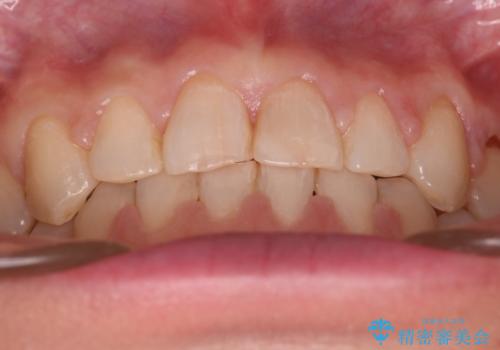

【審美装置】すきっ歯をワイヤー装置で治したい

- 前歯のすきっ歯が気になるということで来院されました。今回は抜歯はしないためワイヤー矯正かインビザライン矯正のどちらでも治療可能でしたが、患者さまのご希望により表のワイヤー装置にて治療をおこないました。

前歯に隙間がいくつかあったため、今回は上下でゴムかけを行いスペースを埋めるための力をかけて閉じました。もう少し早く終了する予定でしたが、ブラッシング不良による歯肉腫脹があり、一部スペースクローズに時間がかかりました。